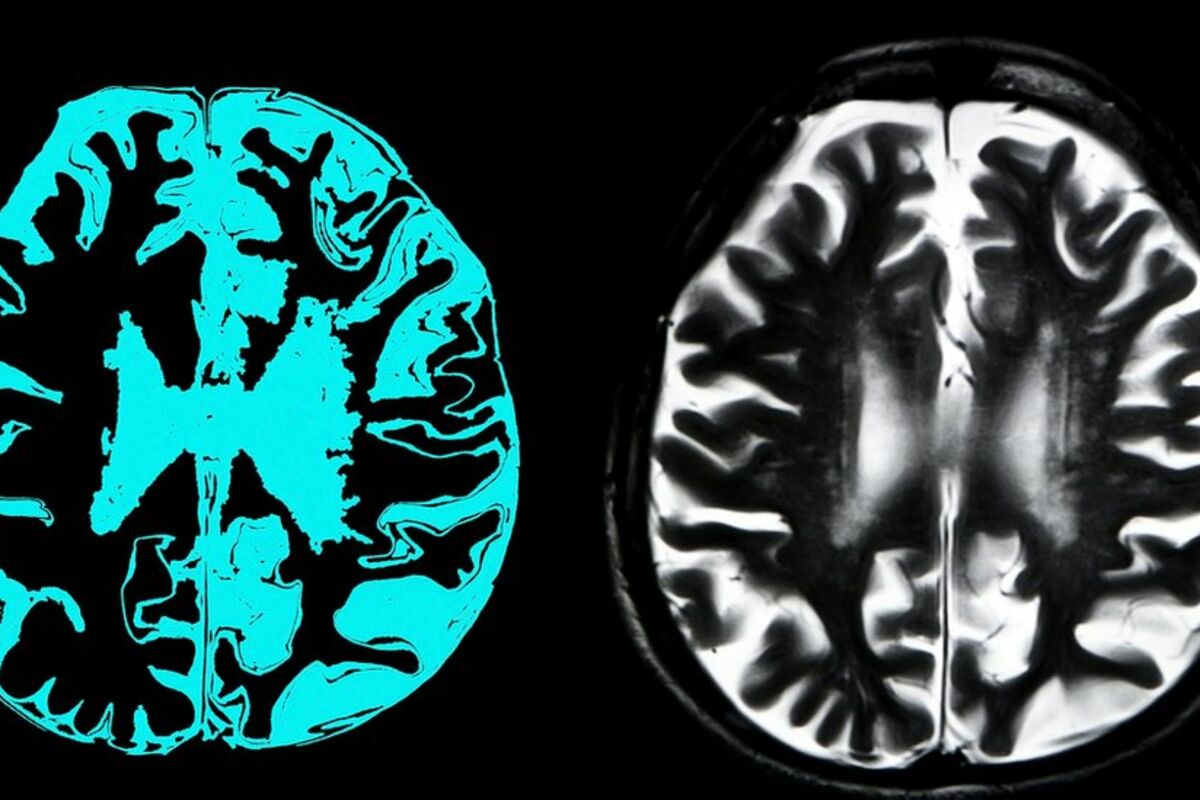

Adukanumab cilja protein amoloid koji formira abnormalne naslage u mozgovima ljudi koji imaju Alchajmerovu bolest. Naučnici smatraju da su te naslage otrovne za moždane ćelije i da je njihovo čišćenje ovim lekom veliki korak napred u lečenju demencije.